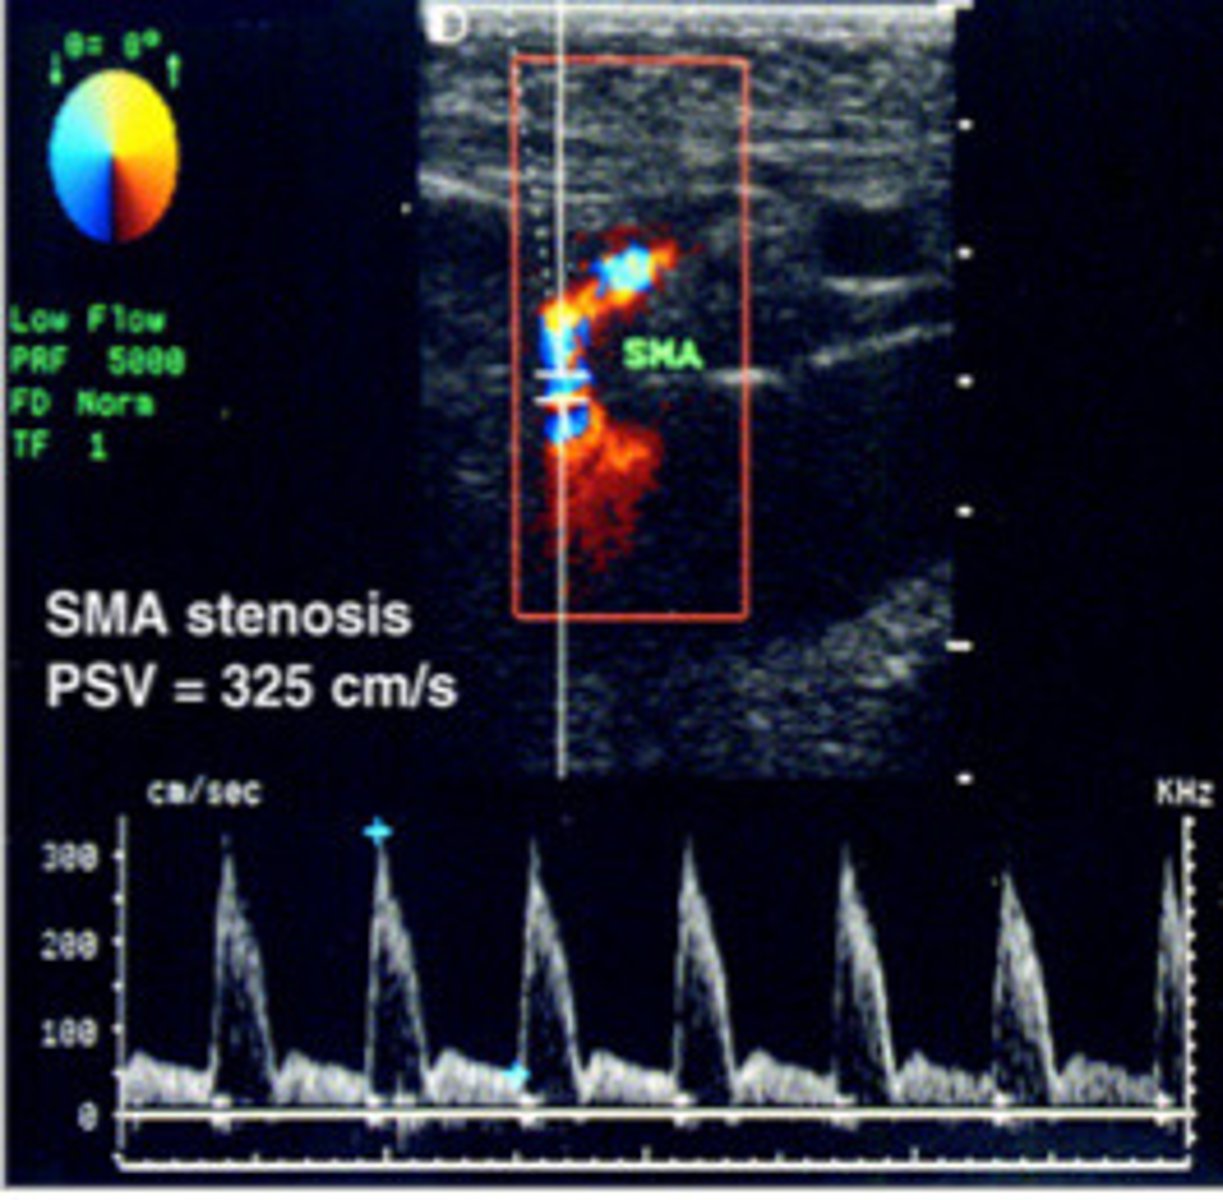

≥275cm/s

What PSV of the SMA would indicate a stenosis of at least 70%

SMA stenosis (note that the PSV is 325cm/s which is higher than our PSV of ≥275cm/s that indicates a stenosis)

What does this image show